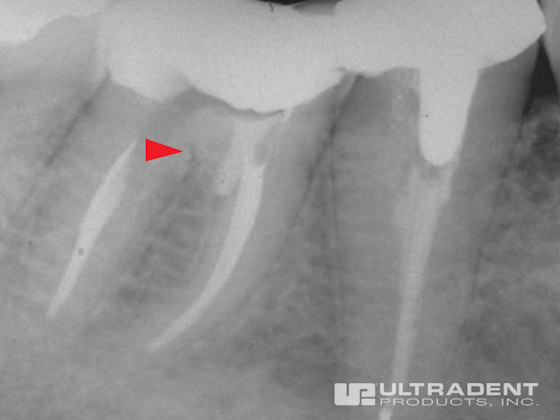

Effective Perforation Repair

Perforation located in the cervical third of the mesial buccal canal.

MTA cement in place showing repair.